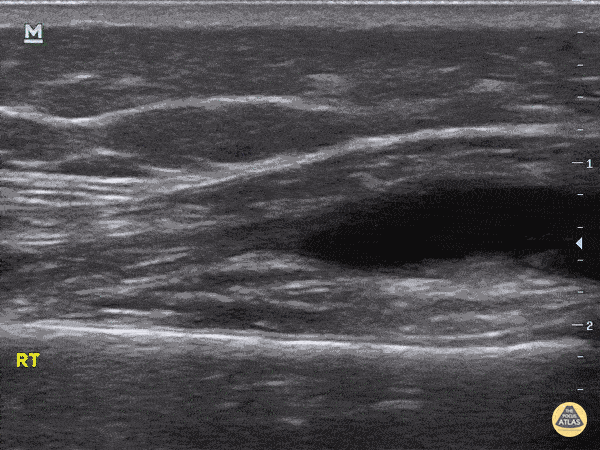

20 month old with right sided limp for 2 days, no fevers, swelling of knee, able to partially range without discomfort, knee aspirate after POCUS purulent, admitted for wash out. Septic vs Lyme's differential. Aspirate yielded 923000 WBC from the cell count, but nothing grew from the cultures. Discharged home on 4 weeks of abx for Lyme, as his titers were positive on Elisa and Western blot. Dr. Sathya Subramaniam - Children's Hospital of Philadelphia